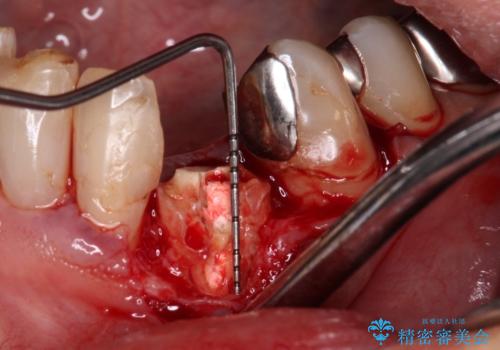

インビザラインは、咬合力の強い方ですと、奥歯が歯肉内にめり込んでしまうため、前歯が強く接触してしまうことがあります。

こちらの方は、奥歯はしっかりと噛んだのですが、歯肉にめり込んでしまったことで、歯肉が腫れやすくなってしまいました。